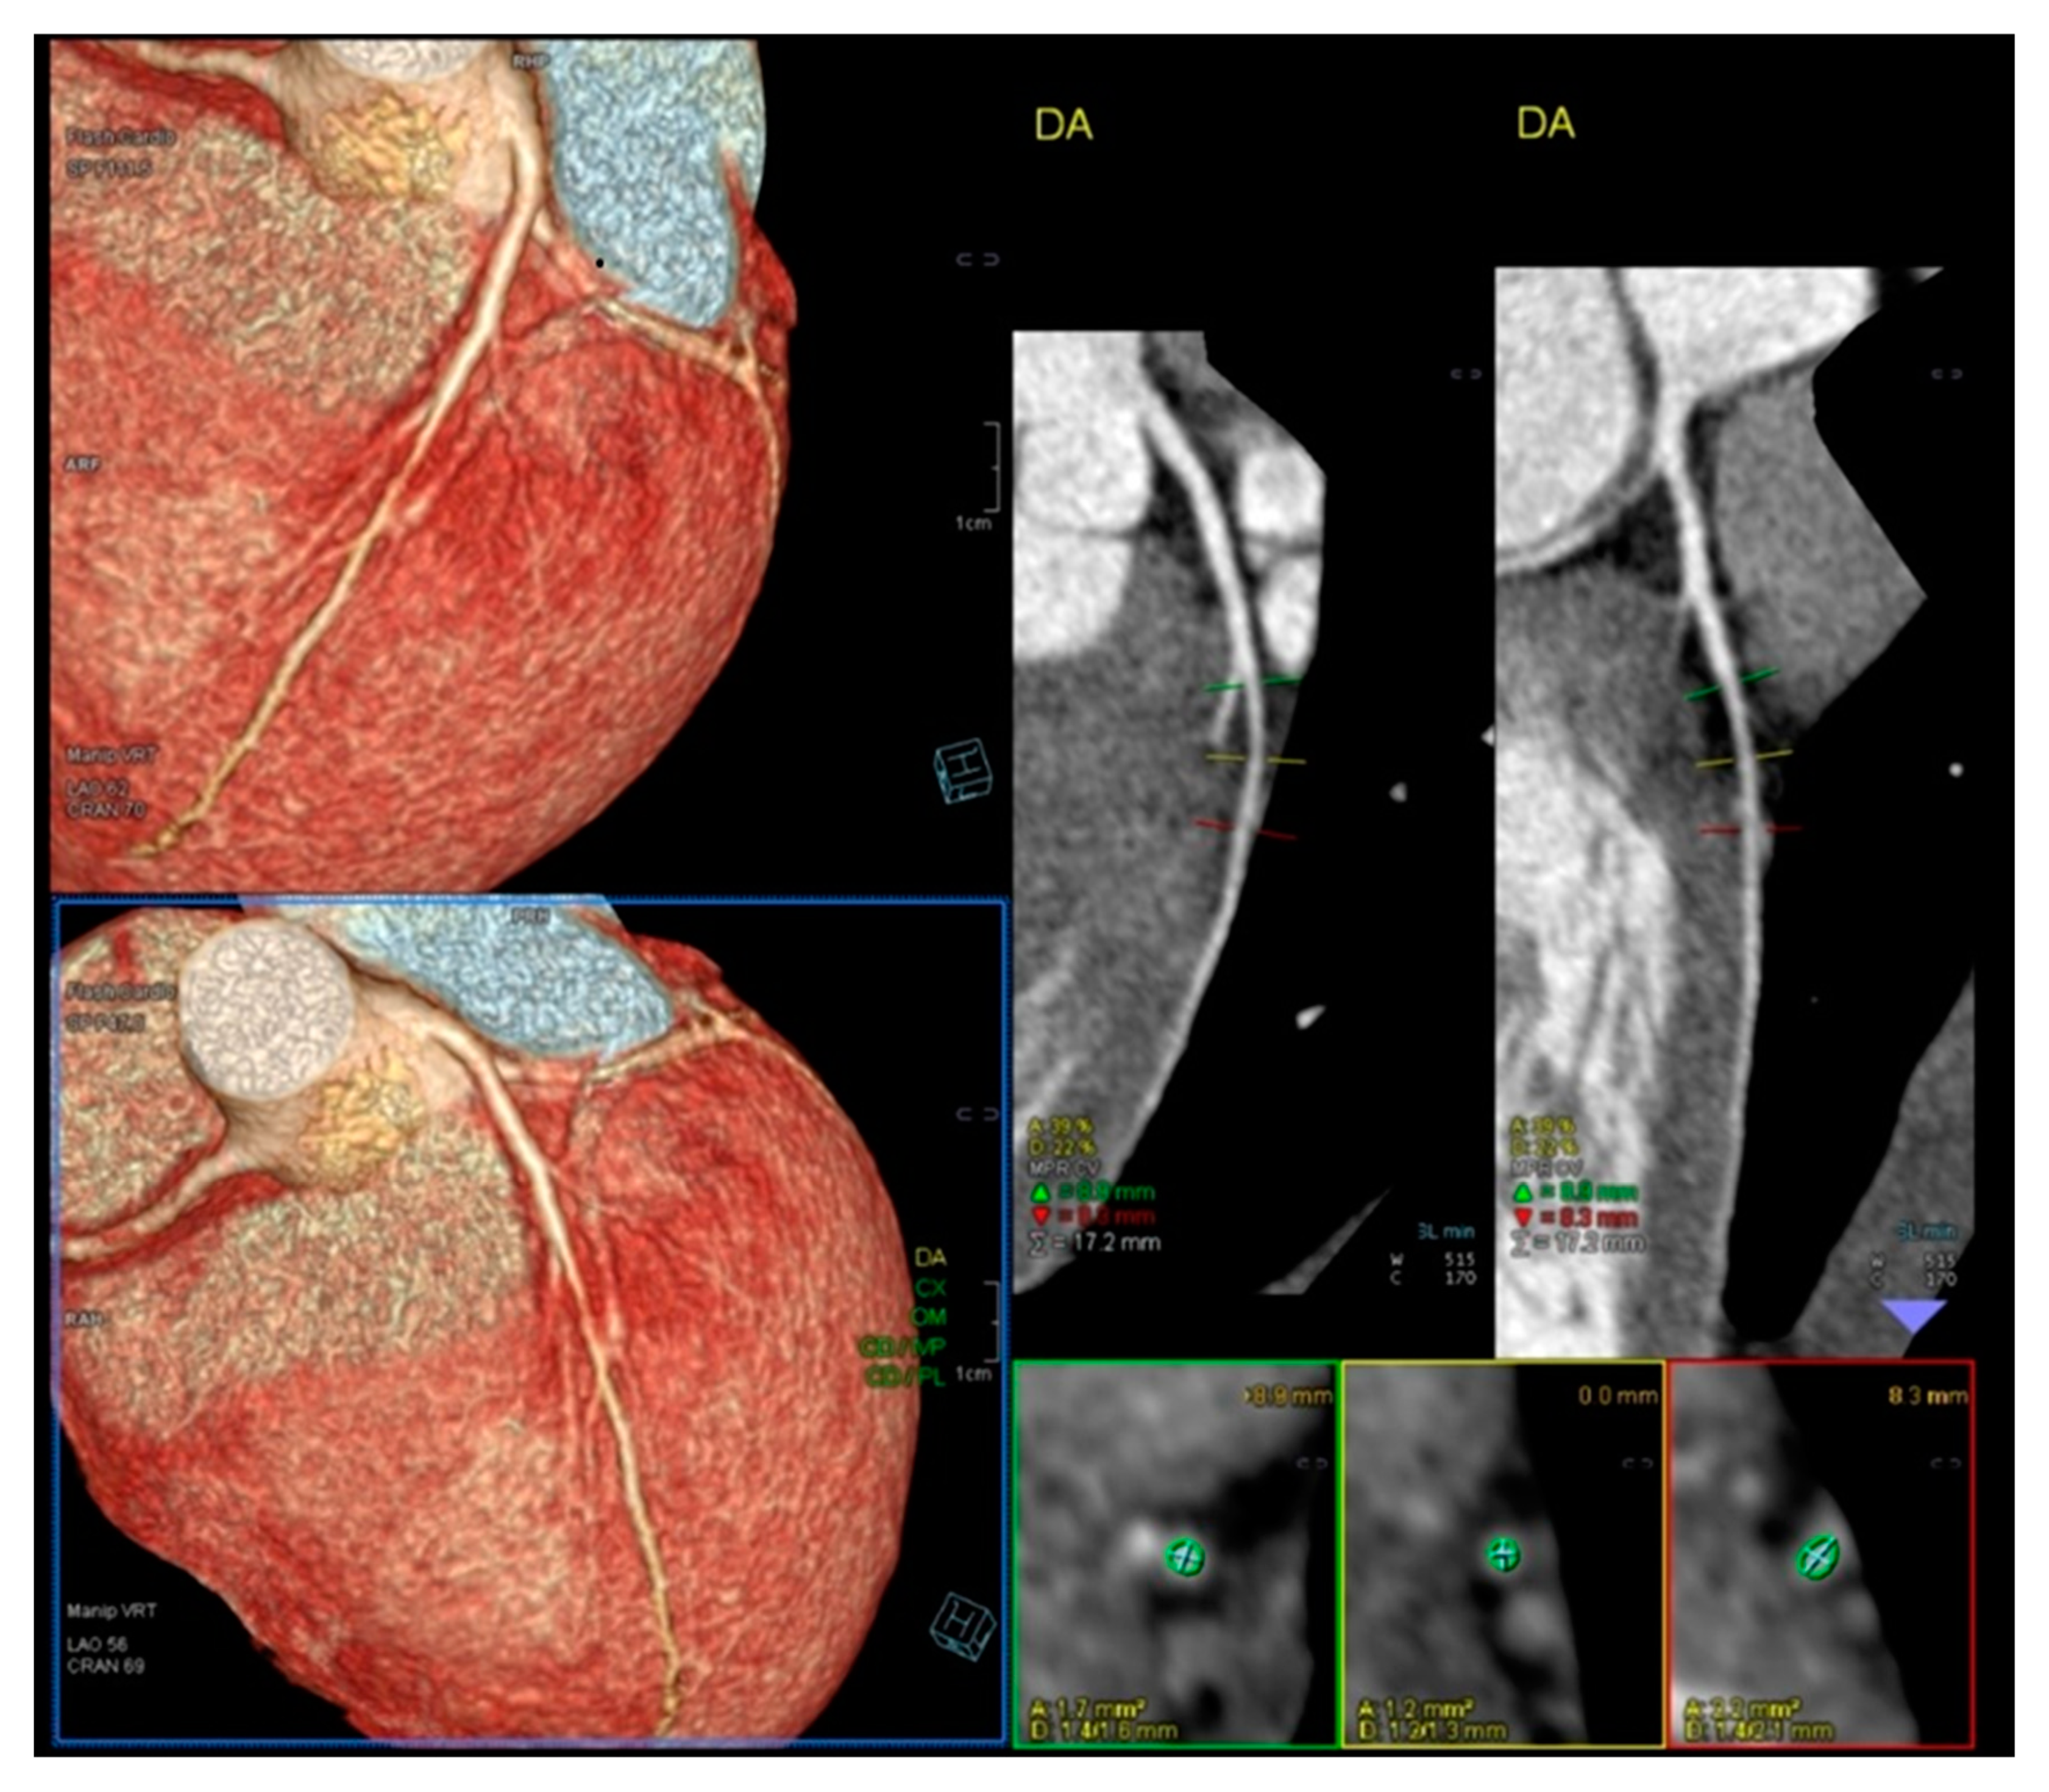

We read with interest the excellent review manuscript from Huang, S.-W. and Liu, Y.-K. [1], which describes that pediatric chest pain is a common chief complaint in the emergency department. Not surprisingly, children with chest pain are usually brought to the emergency department by their parents out of fear of heart disease. However, chest pain in the pediatric population is generally a benign disease. In this review, we have identified musculoskeletal pain as the most prevalent etiology of chest pain in the pediatric population, accounting for 38.7–86.3% of cases, followed by pulmonary (1.8–12.8%), gastrointestinal (0.3–9.3%), psychogenic (5.1–83.6%), and cardiac chest pain (0.3–8.0%). Various diagnostic procedures for cardiac chest pain are commonly used in the emergency department, including electrocardiogram (ECG), chest radiography, cardiac troponin examination, and echocardiography. However, these examinations demonstrate limited sensitivity in identifying cardiac etiologies, with sensitivities ranging from 0 to 17.8% for ECG and 11.0 to 17.2% for chest radiography. To avoid the overuse of these diagnostic tools, a well-designed standardized algorithm for pediatric chest pain could decrease unnecessary examination without missing severe diseases [2,3,4]. Our primary concern is that no attention has been given to exercise-induced intraventricular gradients, which are easily detectable using exercise stress echocardiography and have been associated with chest pain and other symptoms [5,6,7,8,9,10,11,12,13], including in children. We present the case of a 15-year-old boy, a rugby player, who experienced severe chest pain followed by syncope during a match. Upon evaluation at the emergency department, he showed a significant increase in troponin levels. Coronary angiography (Figure 1) and CT angiography (Figure 2) revealed normal results. However, an exercise stress echocardiogram identified a significant intraventricular gradient (Figure 3).

Figure 2. Normal Angio TC of coronary arteries.